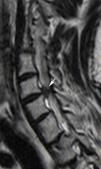

Las técnicas de imagen proporcionan una imagen anatómica excelente de la columna cervical. La elección de cada una de ellas dependerá del escenario clínico y de las alternativas terapéuticas. La radiografía simple sigue siendo fundamental, ya que permite valorar la alineación, las alteraciones óseas y el seguimiento tras el tratamiento. La mayor resolución de contraste de la resonancia magnética permite la valoración de las partes blandas, incluyendo los discos intervertebrales, los ligamentos, la médula ósea y la médula espinal. El papel de la tomografía computarizada en el estudio de la patología degenerativa ha cambiado en los últimos tiempos debido a la gran resolución espacial y su capacidad para visualizar el componente óseo.

Imaging techniques provide excellent anatomical images of the cervical spine. The choice to use one technique or another will depend on the clinical scenario and on the treatment options. Plain-film X-rays continue to be fundamental, because they make it possible to evaluate the alignment and bone changes; they are also useful for follow-up after treatment. The better contrast resolution provided by magnetic resonance imaging makes it possible to evaluate the soft tissues, including the intervertebral discs, ligaments, bone marrow, and spinal cord. The role of computed tomography in the study of degenerative disease has changed in recent years owing to its great spatial resolution and its capacity to depict osseous components.